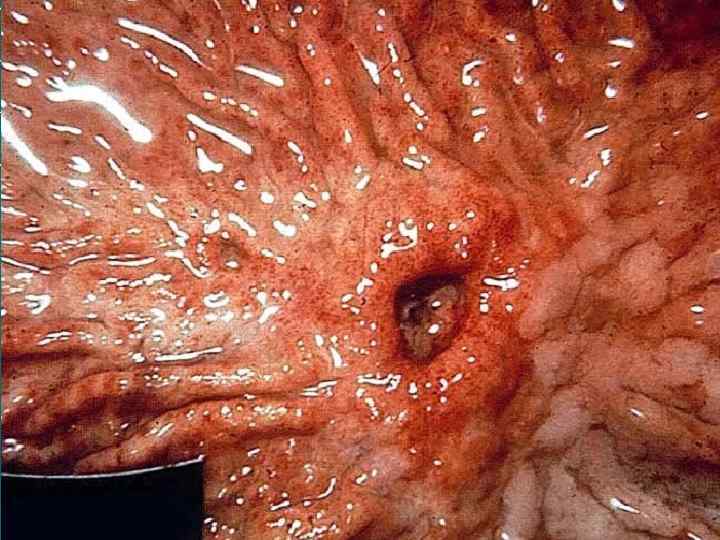

Перфорация язвы желудка и ДПК Анамнез Наличие язвы в анамнезе — у 80 90% больных; «немые» язвы — у 10 15% больных; наличие продромальных симптомов (боль, тошнота, рвота). Характерно острое начало с боли в животе, напряжение мышц брюшной стенки. Начальная реакция организма на перфорацию язвы схожа с патогенезом шока, что связано с ожогом брюшины кислым желудочным соком, излившимся в брюшную полость. В последующем развивается серозно фибринозный, а затем гнойный перитонит.

Клиническая картина Характерна резкая боль в эпигастральной области. Сначала локализуется в верхних отделах живота, при прободении язвы 12 перстной кишки – больше справа от срединной линии, затем по всей правой половине живота, захватывая правую подвздошную область, и далее – по всему животу. Возможна иррадиация болей в плечи и правую лопатку. Может быть рвота «кофейной гущей» или, редко, ярко алой кровью. Характерно исчезновение печеночной тупости из за наличия свободного газа в брюшной полости.

Инструментальная и лабораторная диагностика ОАК: в первые часы количество лейкоцитов нормальное. Лейкоцитоз при развитии перитонита. Рентгенография: свободный газ в брюшной полости (80%). Анализ секреторной функции желудка: повышение кислотности желудочного сока и гиперсекреция (50 55% ). БХАК: повышение показателей билирубина, гамма глобулинов и АЛТ (при перфорации в область печени); Фиброгастродуоденоскопия УЗИ: жидкое содержимое в брюшной полости. КТ Лапароскопия